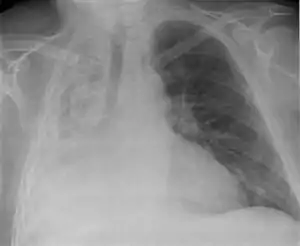

| Atelectasis of a person's right lung | |

Clinically significant atelectasis is generally visible on chest X-ray; findings can include lung opacification and/or loss of lung volume. Post-surgical atelectasis will be bibasal in pattern. Chest CT or bronchoscopy may be necessary if the cause of atelectasis is not clinically apparent. Direct signs of atelectasis include displacement of interlobar fissures and mobile structures within the thorax, overinflation of the unaffected ipsilateral lobe or contralateral lung, and opacification of the collapsed lobe.In addition to clinically significant findings on chest X-rays, patients may present with indirect signs and symptoms such as elevation of the diaphragm, shifting of the trachea, heart and mediastinum; displacement of the hilus and shifting granulomas.[10]